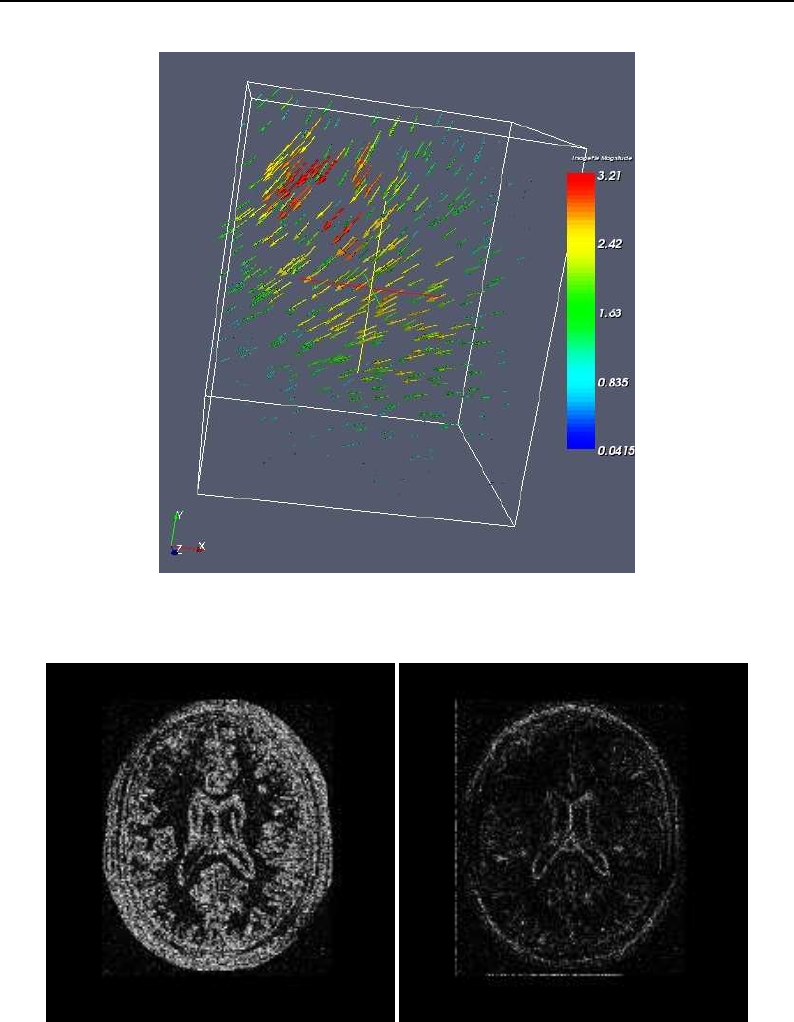

- Visualizing Deformation fields